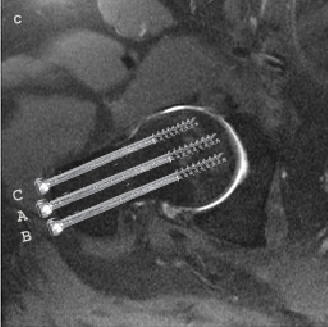

• Intern fiksation med 3 parallelle kannulerede skruer, eller med 2 huls

glideskrue

Ved anvendelse af skruer er der følgende krav:

• At den distale skrue hviler på calcar

• At afstanden fra skruespidsen til den subchondrale knogle skal være ca 5mm

• At der, i fald der indsættes 3 skruer eller flere, skal tilstræbes spredning

af skruerne i sideplanet

• At undgå rotation af caput i forbindelse med isætning af skruer

• At undgå penetration af caput med boret

3 Kannulerede skruer (ved fraktur i det skraverede område) Se skrue

placering på billede A og B: